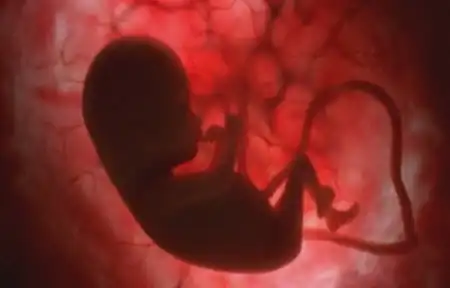

У мамы в животике)